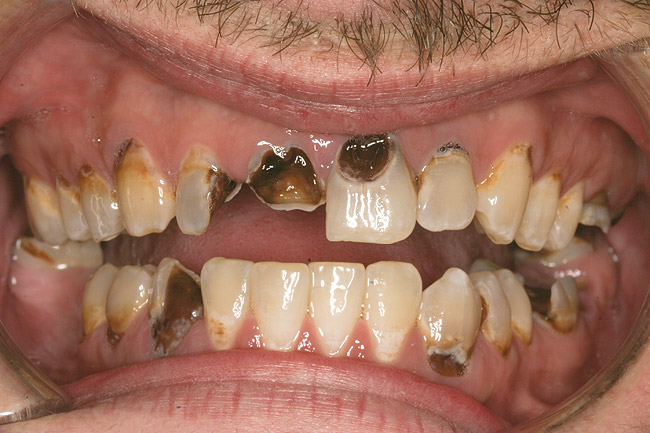

Joe soon learned how to manufacture the drug. His need for meth soon consumed his every thought. He basically lived to do more meth. He admitted that he had made some poor choices. Unfortunately once the addiction kicked in, he no longer had a choice, he had to use. This was his end result (Figure 4 through Figure 6). From these photographs, one might think that he had used the drugs his entire life; however, this progression happened over the course of only about 1 year of smoking the drug. Because of the caustic chemicals (muriatic acid, hydrochloric acid, lithium, etc) his teeth started to blacken, then break.

Figure 4  PRESENTATION CONDITION By the time Joe presented for treatment after serving time in prison and going to rehab, his teeth were completely destroyed by rampant decay. Although some teeth could have been saved, the patient chose to have all of the remaining teeth extracted in order to receive a set of full dentures.

Figure 4

Figure 5  PRESENTATION CONDITION By the time Joe presented for treatment after serving time in prison and going to rehab, his teeth were completely destroyed by rampant decay. Although some teeth could have been saved, the patient chose to have all of the remaining teeth extracted in order to receive a set of full dentures.

Figure 5

Figure 6  PRESENTATION CONDITION By the time Joe presented for treatment after serving time in prison and going to rehab, his teeth were completely destroyed by rampant decay. Although some teeth could have been saved, the patient chose to have all of the remaining teeth extracted in order to receive a set of full dentures.

Figure 6